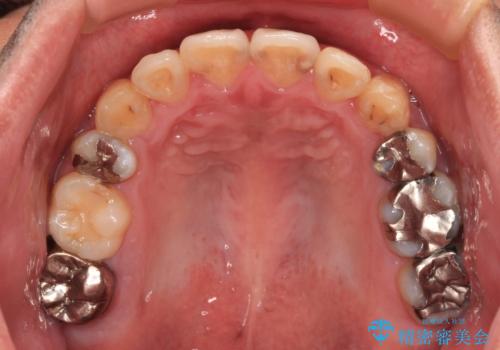

- 上下の八重歯やデコボコを気にして来院された患者様です。

上下ともに八重歯が顕著であったので、上下左右第一小臼歯4本を抜歯し、ワイヤー装置にて矯正治療を行うこととしました。

デコボコが強いことが原因で歯間部に汚れが溜まりやすい状態でしたが、矯正前にできる限り汚れが少なくなるようにブラッシングなどの指導を行い、口腔状態が改善された後にワイヤー装置を装着することとしました。